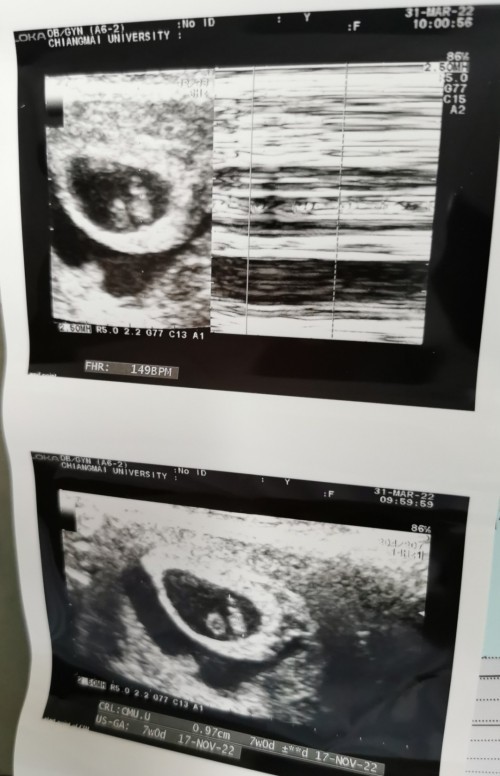

7weeks ค่ะ มีภาวะเลือดออกตลอด เครื่องที่คุณหมอซาวด์ให้ เห็นเส้นเลือดหัวใจ ได้ยินอัตราการเต้นของหัวใจด้วยค่ะ น้ำตาไหลเลยตอนได้ยิน ไม่ต้องกังวลไปนะคะ น้องอาจจะขี้อาย ลูบท้องบอกน้องนะคะ ว่าคราวหน้าขอให้ได้ยินเสียงหัวใจน้องเต้นดังๆ แรงๆเลยนะ ทำใจให้สบายนะคะ ความเครียดจะส่งผลถึงน้องได้ค่ะ ❤️